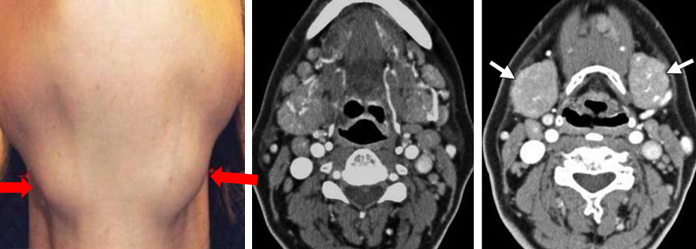

涎腺受累

涎腺受累 PET-CT 表现

腹膜后纤维化

59 岁男性,增强 T1 显示腹主动脉前方软组织增厚,增强后病灶轻度强化。右侧肾盂及上段输尿管积水扩张,CT 增强显示双侧髂总动脉周围不规则软组织应包绕血管,右侧输尿管支架植入